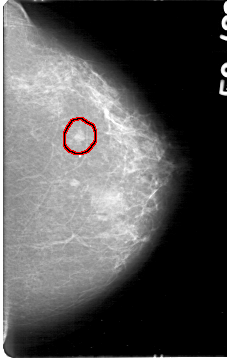

D_4047_1.LEFT_MLO

LEFT_CC LINES 5386 PIXELS_PER_LINE 3391 BITS_PER_PIXEL 12 RESOLUTION 43.5 OVERLAY

FILE: D_4047_1.LEFT_CC.OVERLAY

TOTAL_ABNORMALITIES 1

ABNORMALITY 1

LESION_TYPE MASS SHAPE OVAL MARGINS OBSCURED

ASSESSMENT 0

SUBTLETY 4

PATHOLOGY BENIGN

TOTAL_OUTLINES 1

BOUNDARY